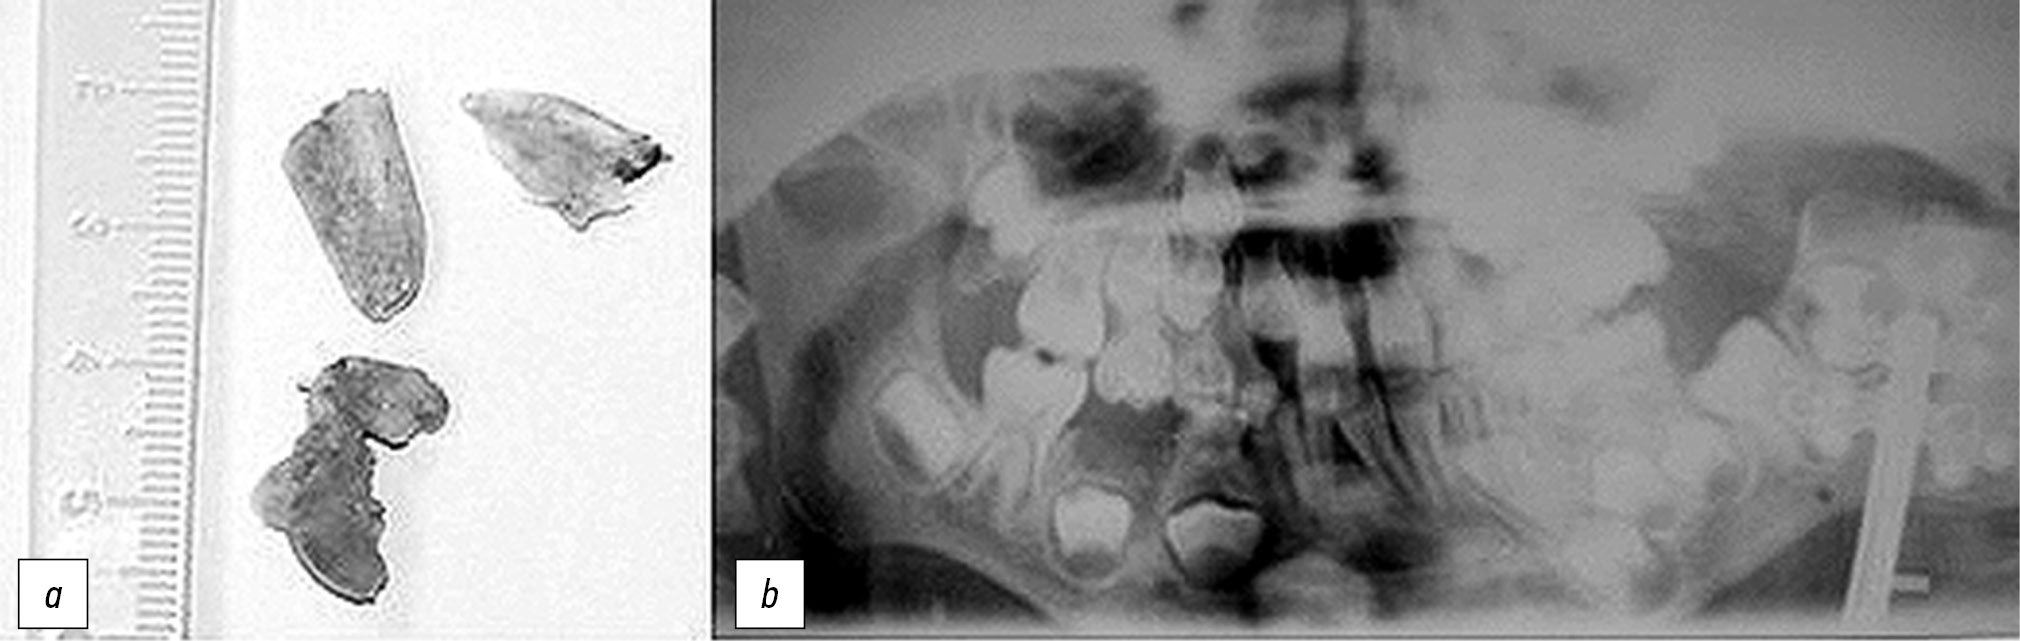

Пациент поступил на лечение в клинику кафедры, где ему выполнили остеотомию ветви нижней челюсти слева с удалением патологических разрастаний; остеотомию в области угла и частично ветви нижней челюсти слева с одномоментным наложением однонаправленного механического КДА (рис. 4).

Рис. 4. Пациент В., 7 лет: a — удалённые во время операции патологические разрастания костной ткани; b — рентгенограмма с компрессионно-дистракционным устройством сразу после операции.

Fig. 4. Patient V., 7 years old: a — pathological bone tissue growths removed during the surgery; b — X-ray of the patient with compression-distraction device immediately after the surgery.

Режим дистракции был дробным — 1 мм в сутки по 0,25 мм за 4 приёма в течение 20 дней, общая величина дистракции составила 2,0 см (рис. 5).

Рис. 5. Рентгенограмма пациента В., 7 лет, на 20-е сутки дистракции, величина дистракции 2,0 см.

Fig. 5. X-ray of the patient V., 7 years old, on the 20th day of distraction, the amount of distraction is 2.0 cm.